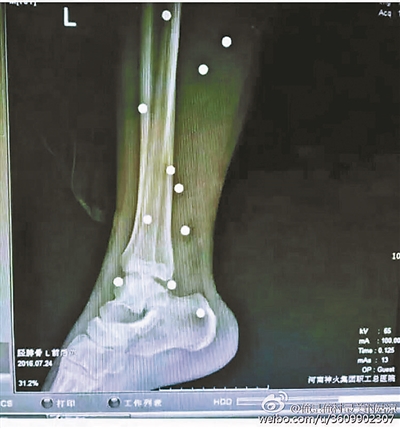

傷者體內取出的鋼珠

爆炸導致鋼珠遍布傷者身體各處

黃明的伯伯對北青報記者表示,由于黃明直接踩到了爆炸物,所以傷情最為嚴重,“他的腿被炸斷,身體內被炸進了40多顆鋼珠。手術后已經(jīng)從體內取出29顆鋼珠,還有十多顆鋼珠沒有取出來?!备鶕?jù)黃明的入院記錄,他全身有多處爆炸傷,且全身多處異物存留。

爆炸發(fā)生時,陳浩的位置與黃明靠得很近,因此也受傷較重。他告訴北青報記者,經(jīng)過10多個小時的手術后,醫(yī)生從他身體里取出了12顆鋼珠。目前,他和黃明兩人經(jīng)過手術后,已從重癥監(jiān)護室轉至普通病房。其余三人中,陳剛的臀部受傷,當天晚上在醫(yī)院清理完傷口后便回了家,而同行的兩名女生身上有一些擦傷。